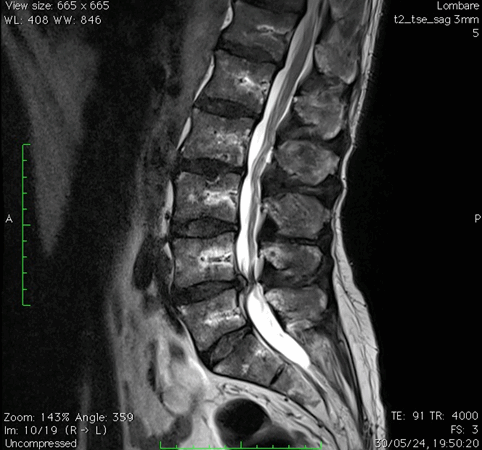

Risonanza magnetica lombare pre-operatoria

Intervento chirurgico eseguito:

PROCEDURA PLIF: POSTERIOR LUMBAR INTERBODY FUSION

Stabilizzazione vertebrale percutanea L4-L5 + introduzione di cage intersomatica PLIF Radiografia lombare post-operatoria